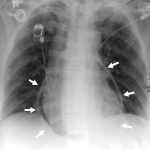

Ung Thư Vòm Họng | Bài giảng CĐHA

Ung thư biểu mô hầu-mũi (Nasopharyngeal carcinoma) tên thông thường là K vòm. 82% K vòm xuất phát từ rãnh sau bên của thành hầu (hố Rosenmuller), 12% phát sinh từ đường giữa. Tỷ lệ nam:nữ = 3:1, tuổi thường gặp 40-60T…